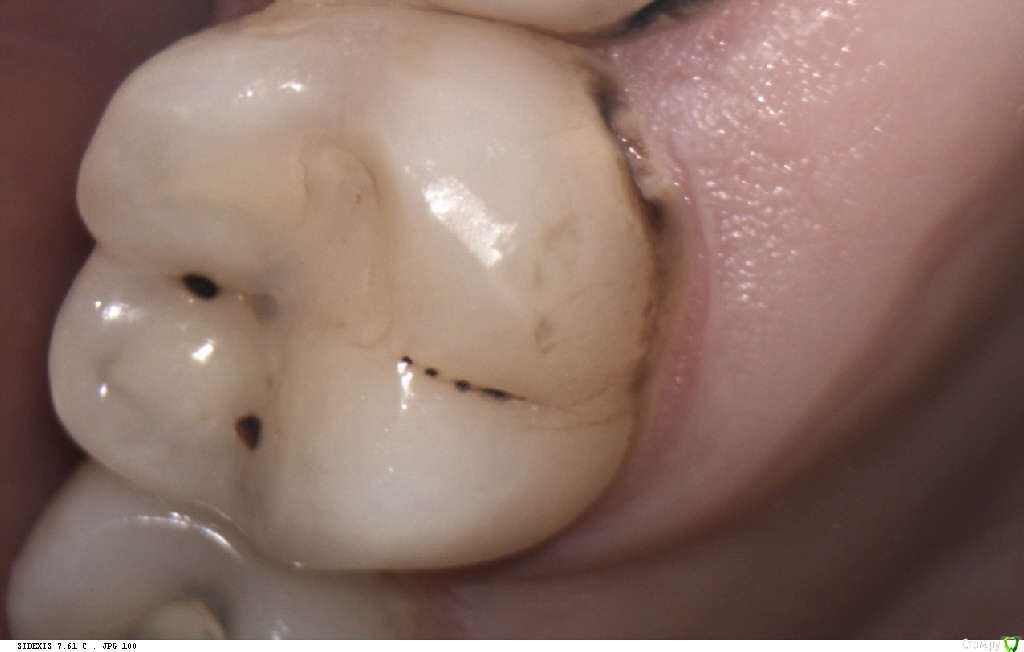

Pan Опубликовано 6 мая, 2017 Поделиться Опубликовано 6 мая, 2017 (изменено) типичная локализация кариеса при плохой гигиене и злоупотреблении в питании фастфуда. Ну понятно, что всё это на фоне сниженной кариесрезистентности. Первым делом нужно объяснить девушке значимую роль питания и гигиены в развитии кариозных процессов. Изменено 6 мая, 2017 пользователем Pan 1 Ссылка на комментарий

Pan Опубликовано 11 мая, 2017 Поделиться Опубликовано 11 мая, 2017 (изменено) Деструкция эмали (в типичных для зубного налета местах) произошла значительно ранее ( разве нужно еще раз говорить об истинных причинах, способствующих этому процессу?) Потом, конечно, индивидуум (взрослея) изо всех сил старается и отсутствие признаков гингивита(если хотите) тому подтверждение. Но, увы, процесс уже запущен... Вы конечно же не хотите оспорить тот факт, что деструкцию эмали (кариес) вызывают бактерии зубного налета. Изменено 11 мая, 2017 пользователем Pan Ссылка на комментарий